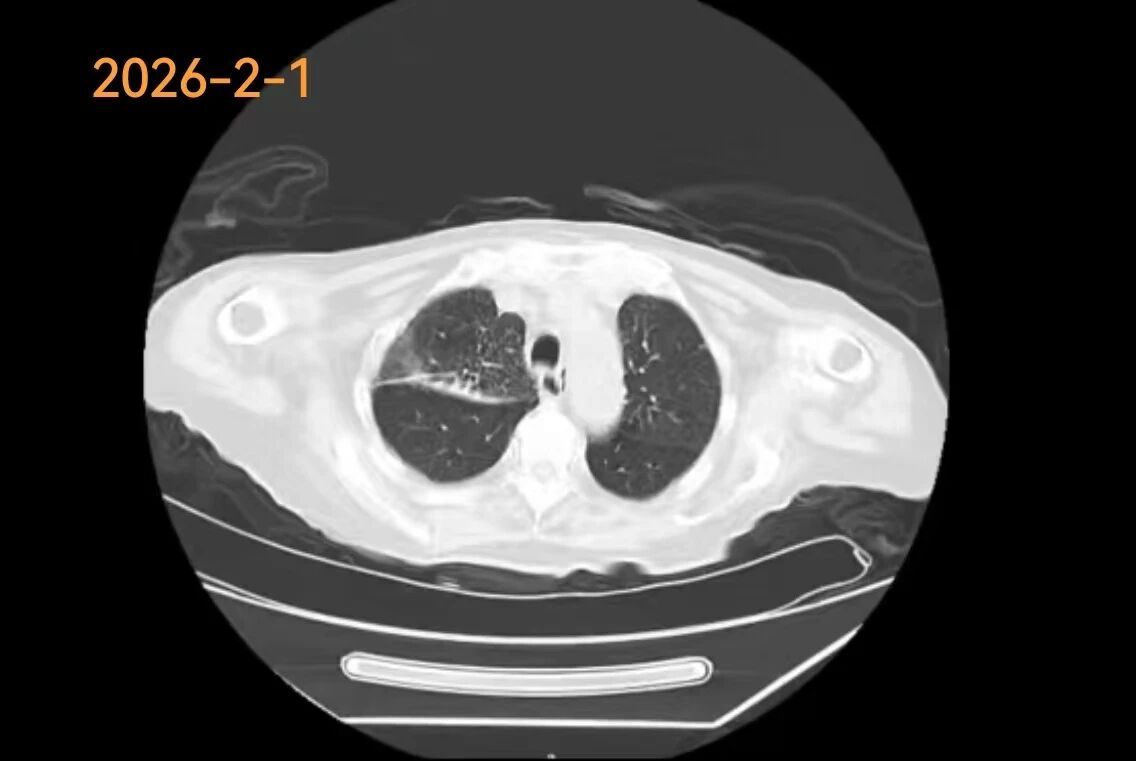

3、新疆医院多学科联手完成高难度经皮肺穿刺

近日,新疆医院呼吸与危重症医学科、胸外科、放射影像中心联手,完成1例高难度经皮肺穿刺活检术。手术经过影像科精准定位,呼吸与胸外科医生在CT引导下,以毫米级的精度调整进针角度与深度,避开“红线”,直取病变核心,最终抵达目标,成功取材。